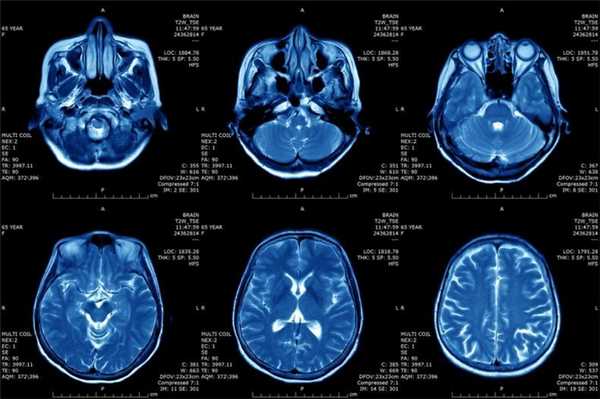

Что показывает МРТ

Магнитно-резонансная томография или МРТ - это сфокусированный метод, который проводит очень детальное обследование. Диагностическая точность МРТ превышает УЗИ и во многих случаях КТ, за исключением сканирования полых органов (легких, желудка, кишечника) и костей. МРТ является золотым стандартом диагностики:

- заболеваний головного и спинного мозга;

- патологий суставов;

- межпозвоночных дисков;

- сердца и сосудов;

- болезней гинекологического, проктологического и урологического характера.

В отличие от быстрого КТ и УЗИ, магнитно-резонансное обследование требует времени - в среднем пациенту нужно лежать в томографе и соблюдать неподвижность 30-60 минут.

Принцип работы МРТ основан на эффекте ядерного магнитного резонанса. МР томограф в своей конструкции имеет мощный магнит, который создает магнитное поле, и датчик, который подает радиочастотные сигналы. В такой ситуации протоны атомов водорода начинают колебательные движения, выделяя при этом импульсы. Их улавливает компьютер томографа и преобразовывает в трехмерные изображения. Чем больше воды содержится в клетках ткани, тем детальней получается ее изображение. Поэтому на МРТ хорошо отображаются органы с большим содержанием воды: МРТ головного мозга, МРТ спинного мозга, МРТ глазных орбит, МРТ органов малого таза, МРТ позвоночника, МРТ суставов, и плохо визуализируются органы с большим содержанием воздуха МРТ органов грудной клетки или кости.

Основы преимуществом МРТ перед КТ и рентгеном является отсутствие в ходе сканирования какого-либо излучения. А вот недостатком этого метода диагностики будет ряд ограничений - наличие ферромагнитного металла в теле пациента и имплантированных в организм водителей ритма, несовместимых с МРТ.

Магнитно-резонансная томография

В основе МРТ лежит явление магнитного резонанса, основанного на переизлучении радиоволн, взаимодействующих с атомами водорода, в избытке содержащимися в организме человека. Эти переизлученные электромагнитные волны улавливаются датчиком МР-томографа, усиливаются и в виде цифровых изображений появляются на экране монитора. Это безвредный и абсолютно безопасный для здоровья человека метод лучевой диагностики, так как в основе получения изображения отсутствует рентгеновское излучение, поэтому МРТ можно проходить неограниченное количество раз, с любым интервалом.

Существенное преимущество МР-томографии перед КТ заключается в том, что она не противопоказана беременным во II и III триместре и совершенно безопасна для детей. В МРТ исследуемая область сканируется в трех проекциях, что позволяет врачу-рентгенологу в полной мере оценить состояние тканей и органов исследуемой области, а высокая контрастность изображения и пространственное разрешение позволяют визуализировать серое и белое вещество головного мозга, оценивать состояние костного мозга и мягких тканей различной локализации. Кроме того, метод МРТ позволяет получать изображения сосудов головного мозга и сосудов шеи без введения контрастного препарата.

Конечно, как и многие другие методы исследования, МР-томография имеет ряд противопоказаний. Однако, если внимательно ознакомиться с ними, можно заметить, что в основном они связаны с наличием металлсодержащих имплантов (не обладающие магнитными свойствами устройства противопоказанием не являются), а также с выраженной клаустрофобией. Таким образом, в большинстве случаев МРТ может стать наиболее оптимальной и совершенно безопасной альтернативой компьютерной томографии и рентгенографии.